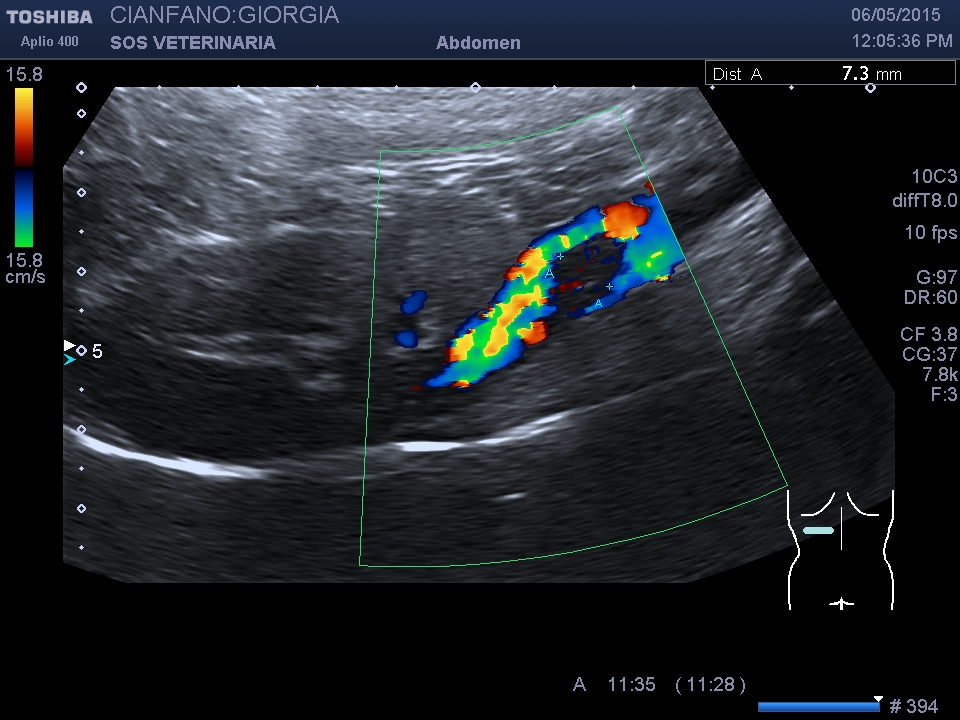

L’invasione cavale puo’ essere di tessuto neoplastico o iniziale formazione di un trombo.

Eseguita ceus e tac

Si conferma l’invasione neoplastica